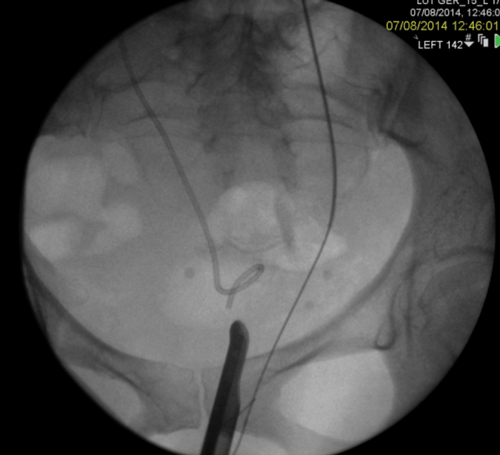

Figure 2: A Rendezvous in a patient with prostate cancer obstructing the left ureteric orifice, a partial staghorn calculus in the left kidney and left lower ureteric stones. Resection of tumour over ureteric orifice and antegrade wire.